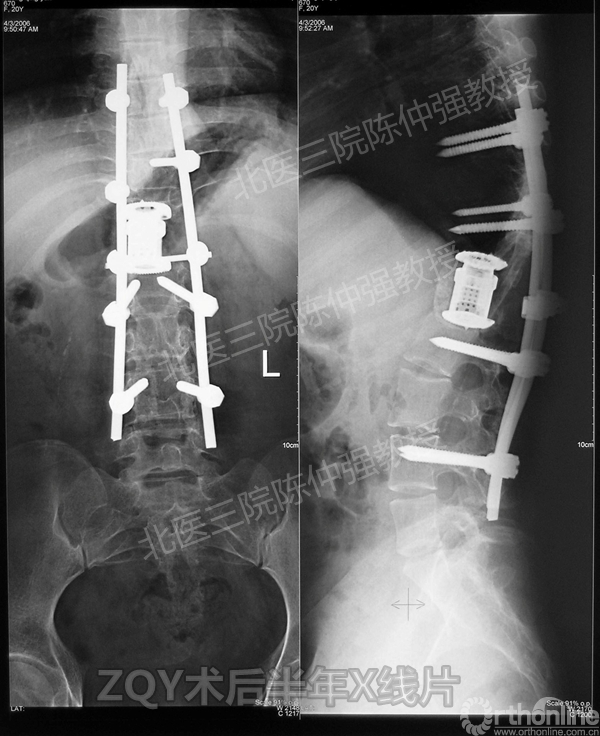

ZQY术后半年

患者女性17岁,胸腰椎陈旧结核性侧后凸畸形,局部呈“麻花状”扭转,无神经功能受损表现。2005年,陈仲强教授带领团队实施后路+侧前方联合入路脊柱节段切除、双轴旋转矫形术。术后患者外观显著改善,神经功能正常。术后随访证实患者截骨矫形节段骨性融合良好,矫形效果持续良好。